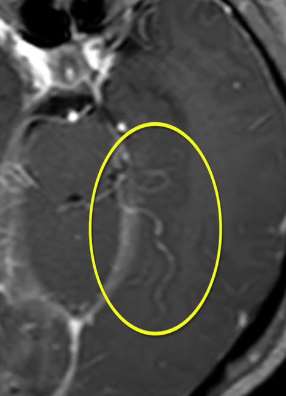

江苏一少女腹痛就医 检查发现卵巢内长20cm肿瘤